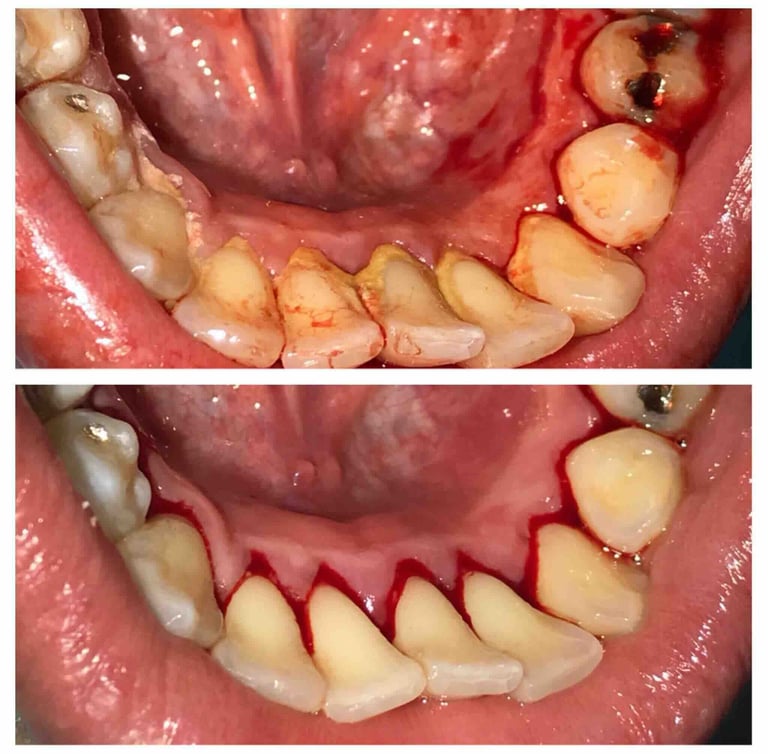

Deep cleaning, also known as scaling and root planing, is used to treat gum disease by removing plaque and bacteria from below the gum line and smoothing the tooth roots to help gums heal properly. Depending on the severity of the condition, the treatment may be completed in sections (such as half-mouth or quadrant visits) to ensure comfort and thorough care. After deep cleaning, ongoing periodontal maintenance visits every 3–4 months are essential to keep gum disease under control, as regular cleanings are not sufficient once periodontal issues are present.

Treatment Results

Scaling — removing buildup from below the gumline

Root planing — smoothing the roots to help gums heal